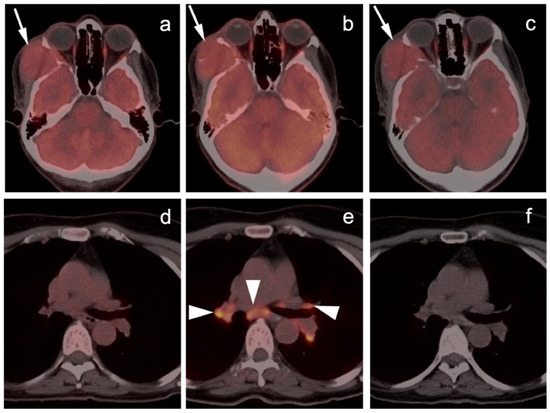

- Mankia, S.K.; Miller, R.F.; Edwards, S.G.; Ramsay, A.; Lee, S.M. The Response of HIV-Associated Lymphadenopathic Kaposi Sarcoma to Highly Active Antiretroviral Therapy Evaluated by 18F-FDG PET/CT. Clin. Nucl. Med. 2012, 37, 692–693. [Google Scholar] [CrossRef]

- Morooka, M.; Ito, K.; Kubota, K.; Minamimoto, R.; Shida, Y.; Hasuo, K.; Ito, T.; Tasato, D.; Honda, H.; Teruya, K.; et al. Whole-body 18F-fluorodeoxyglucose positron emission tomography/computed tomography images before and after chemotherapy for Kaposi sarcoma and highly active antiretrovirus therapy. Jpn. J. Radiol. 2010, 28, 759–762. [Google Scholar] [CrossRef]

- Polizzotto, M.N.; Millo, C.; Uldrick, T.S.; Aleman, K.; Whatley, M.; Wyvill, K.M.; O’Mahony, D.; Marshall, V.; Whitby, D.; Maass-Moreno, R.; et al. 18F-fluorodeoxyglucose Positron Emission Tomography in Kaposi Sarcoma Herpesvirus–Associated Multicentric Castleman Disease: Correlation with Activity, Severity, Inflammatory and Virologic Parameters. J. Infect. Dis. 2015, 212, 1250–1260. [Google Scholar] [CrossRef] [Green Version]